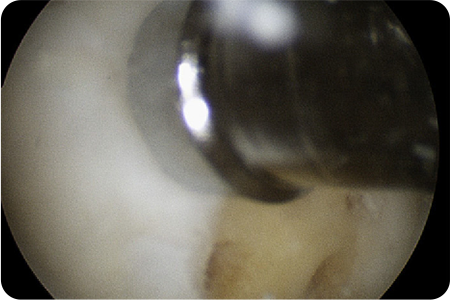

관절내시경을 통해 손상된 연골을 정리하고,

이식할 부위를 다듬습니다. 채취한 줄기세포를

특수 처리 후 손상된 관절 부위에 도포

하고

마무리합니다.